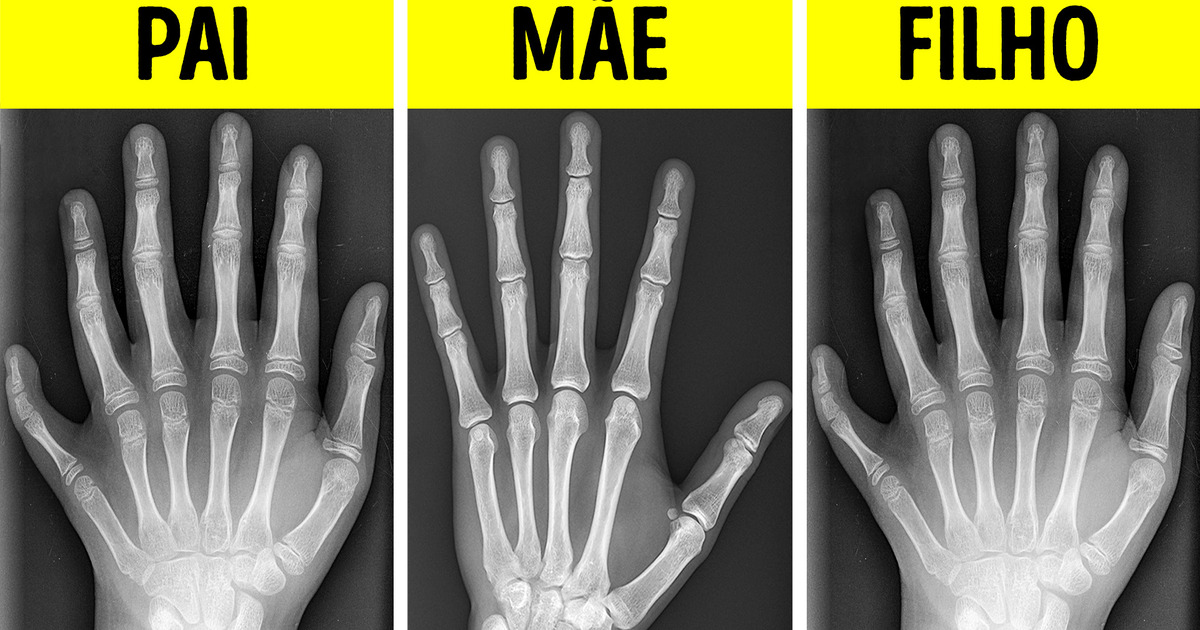

Os gêmeos podem nascer com vários meses de diferença. Os olhos do avestruz são maiores que o cérebro dele. Um bebê tem muitas chances de ter mais de 5 dedos na mão se um de seus pais tiver essa condição. E então, será que esses fatos são verdadeiros ou historinha pra boi dormir? Vamos descobrir!

A polidactilia (uma condição na qual a pessoa tem mais de 5 dedos na mão ou no pé) pode ser geneticamente hereditária. Ou seja, pode ser transmitida dos pais para os filhos.